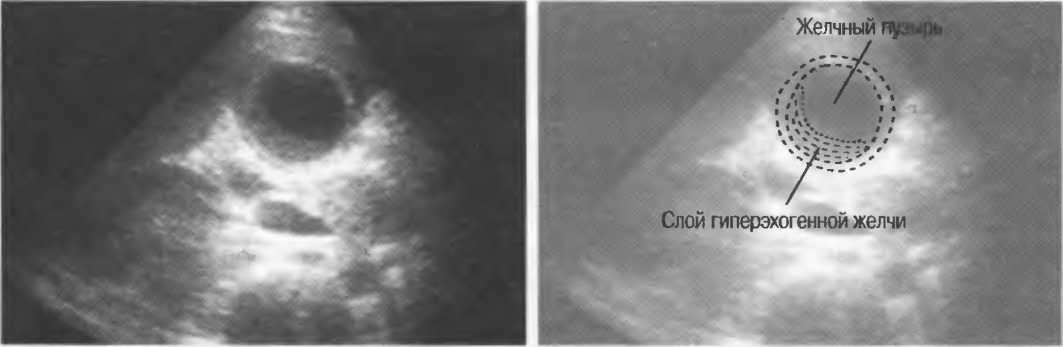

Взвесь(осадок) |

Эхогенная внутренняя структура различных размеров, формы, с неровным контуром в объемной структуре, содержащей жидкость. Может быть подвижной, изменяющейся при перемене положения тела пациента или при его движении. |

Ультразвуковые отражения от тканей с различным акустическим сопротивлением в одном органе. Внутренняя эхоструктура может, например, появляться в желчном пузыре при наличии конкрементов, взвеси в полости абсцесса. |

Гиперэхогенный (гиперэхоидный) |

Таким образом описываются ткани, создающие более яркие отраженные эхосигналы, чем рядом расположенные ткани, например кости, паранефральная клетчатка, стенка желчного пузыря, цирротическая печень (по сравнению с нормальной печенью). |